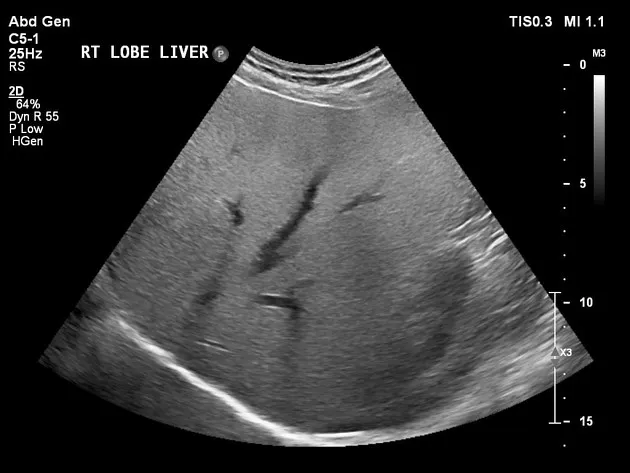

Injúria Renal Aguda (revisão Lancet 2025)